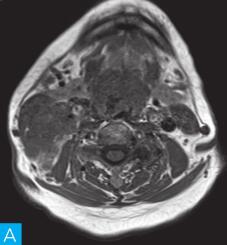

喉咽部MRI检查:病人采取仰卧位,横断位扫描为主,包括T1WI、T2WI及T2WI脂肪抑制序列,扫描范围自鼻咽部至喉咽以下,扫描层厚为3.5mm、层间隔0.35mm,矩阵512×512;辅以冠状位T2WI,矢状位T2WI序列及脂肪抑制序列,平扫后行横断位、冠状位及矢状位的增强扫描,造影剂量0.2ml/kg。见图1。

图1 咽喉部MRI:A.喉咽部MR横断面平扫T1WI;B.喉咽部MR横断面T2WI;C.喉咽部MR横断面T2压脂;D.喉咽部MR横断面增强T1WI;E.喉咽部MR冠状面T2WI;F.咽喉部MR冠状面增强T1WI

MRI平扫可见右侧扁桃体较大的软组织肿块,T1WI呈稍低信号,T2WI呈稍高信号,信号较均匀,T2WI压脂序列上呈高信号,病变与右侧咽扁桃体及舌根部分界不清,左侧咽扁桃体肿大,口咽腔明显变形狭窄,病灶延伸至喉前庭;双侧锁骨上窝及颈血管鞘周围间隙内可见多发大小不等的肿大淋巴结,大部分肿大淋巴结信号较均匀,呈稍高信号,边界清楚,右侧颈部间隙内个别肿大淋巴结内见少量斑片状液化坏死区;增强扫描后下咽部病变及双侧颈部间隙内的肿大淋巴结均呈明显的较均匀强化,提示该两处占位病变的血供较为丰富,且可能为同源性病变,因此采取“一元论”诊断思维进行分析更为合理。

(1)发现病变与认证:扁桃体及颈部病变较为容易发现,主要是分析两方面:一是仔细观察咽部有无原发病变,原发病变的形态及信号;二是评价淋巴结的分布,淋巴结的信号及生长特点。本病例基本征象为扁桃体病变信号均匀,无坏死,颈部淋巴结分布广泛,信号均匀。

(2)定位诊断:对于本病例来说,发现两处病变,包括咽部和颈部。咽部的病变位于扁桃体,延伸至喉咽腔,口咽腔和梨状窝受压变窄。颈部的病变为多发淋巴结增大,淋巴结广泛分布于Ⅱ~Ⅴ区。

本病例的特点为右侧扁桃体肿块,病变边界较清楚,表面光滑,信号均匀。双侧颈部间隙内多发肿大淋巴结,淋巴结围绕颈动脉鞘,部分病变融合倾向,广泛分布于Ⅱ~Ⅴ区,增强后病变较明显强化。

该病例首先对病变进行定位,包括咽部的和颈部的。咽部的病变:病变位于扁桃体,延伸至喉咽腔,口咽腔和梨状窝受压变窄(引起异物感和吞咽困难的原因)。颈部的病变:多发淋巴结增大,淋巴结广泛分布于Ⅱ~Ⅴ区。扁桃体病变的信号特征:扁桃体病变表面光滑,提示黏膜完整,病变来源于黏膜下,病变信号均匀,无坏死,进一步支持病变来源于黏膜下。颈部淋巴结病变的特征:淋巴结分布广泛,信号均匀(可以初步排除结核和转移,后两者容易坏死),围绕颈动脉鞘,但是不侵犯颈动脉鞘(转移容易侵犯颈动脉鞘),部分淋巴结融合倾向(结核淋巴结增大,无融合倾向,而且容易坏死),病变中度强化,进一步支持颈部淋巴瘤的诊断。诊断原则:首先仔细观察咽部有无原发病变,原发病变的形态及信号,尤其黏膜是否完整。其次评价淋巴结的分布,淋巴结的信号及生长特点。